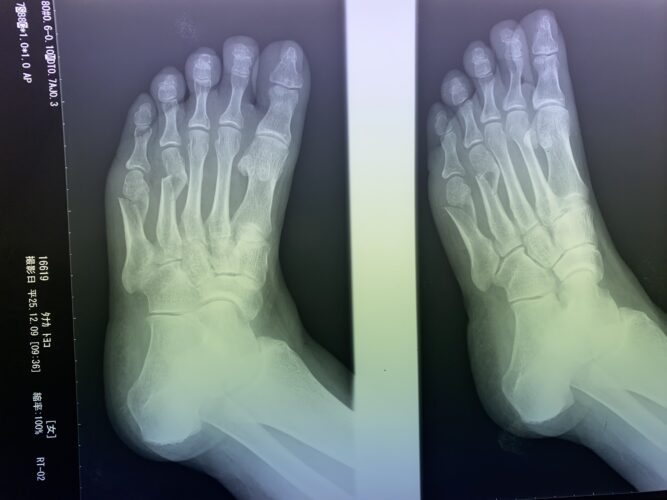

第5中足骨骨折の1症例について